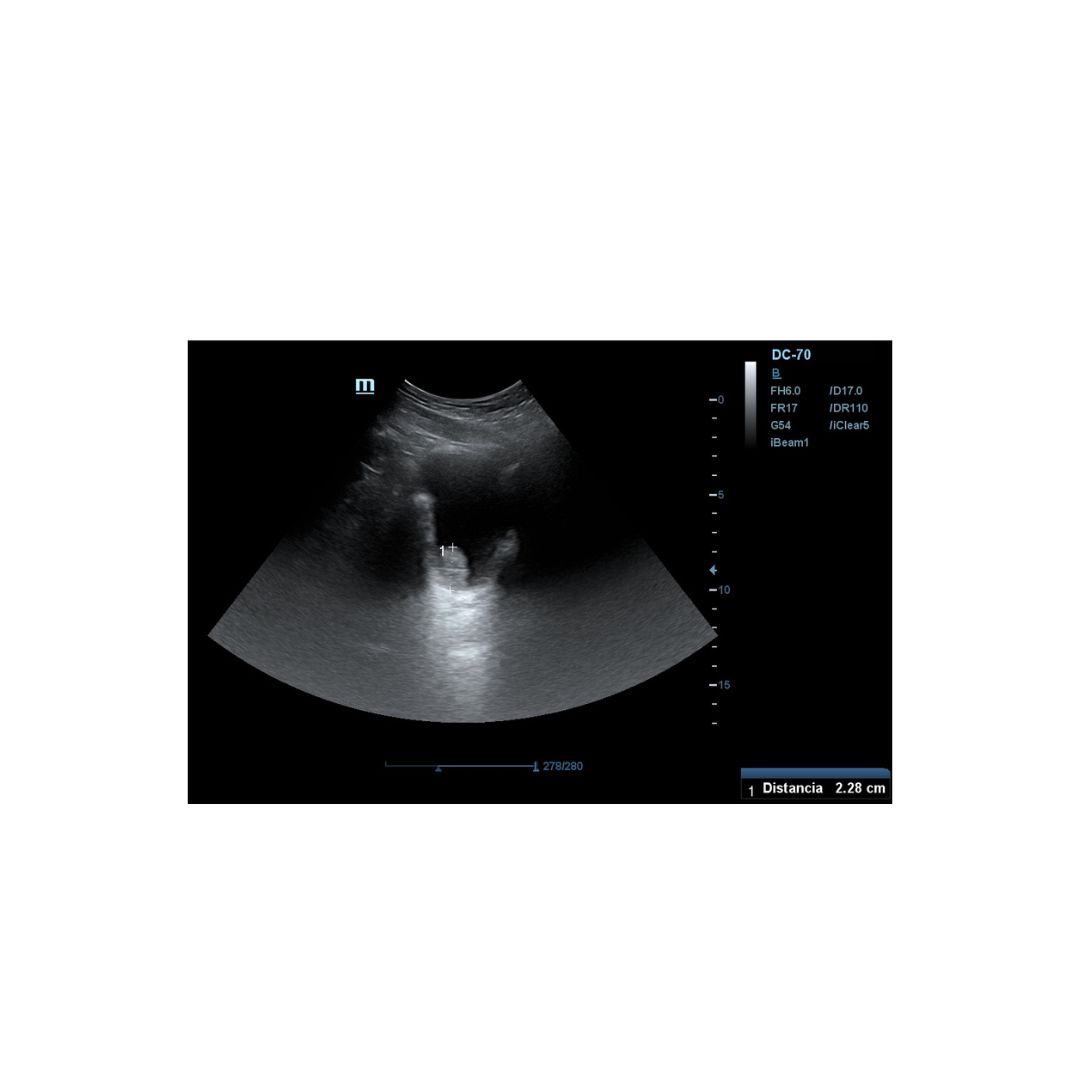

Es derivado a consulta de ecografía de nuestro centro de salud, donde realizamos Ecografía clinica abdominal, apreciándose imagen hiperecogénica pediculada en pared posterior izquierda de la vejiga vejiga, fija, que mide 2,26 mm aproximadamente en su eje mayor, sin captación Doppler.